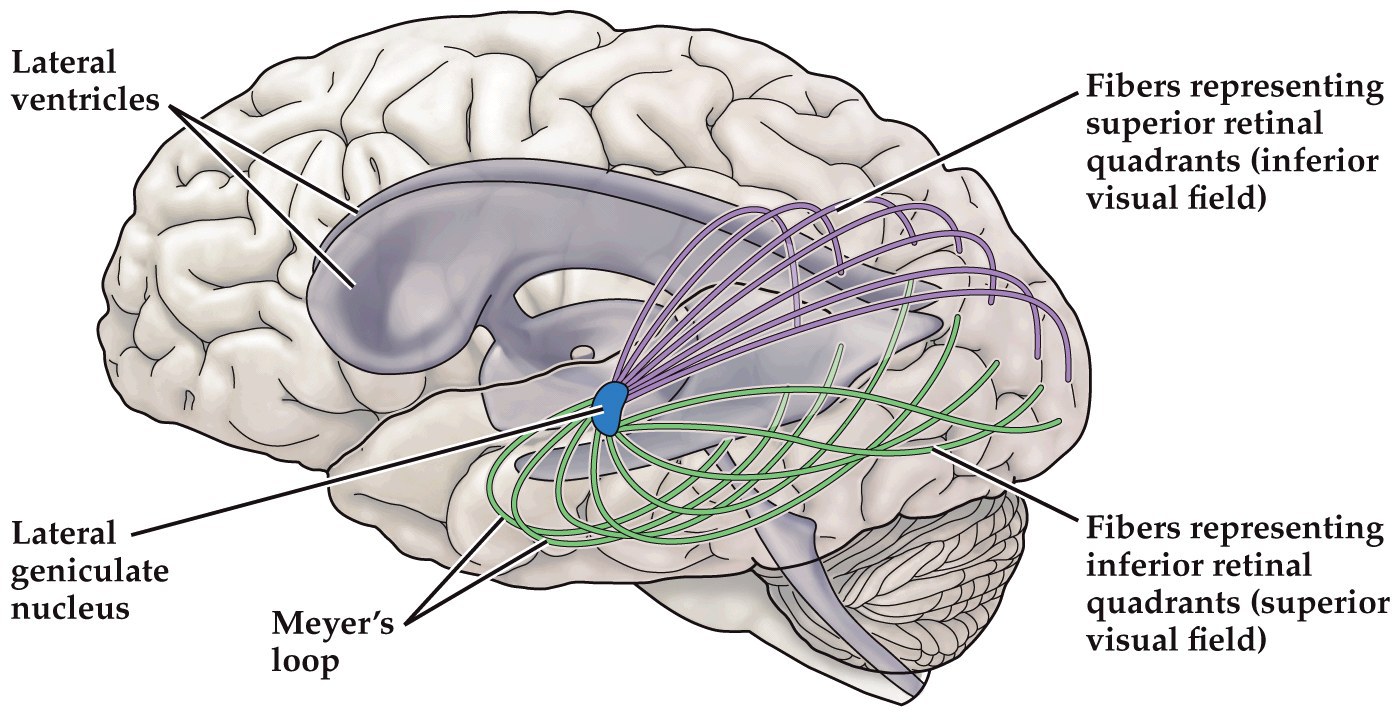

- Superior and inferior visual fields take different routes to the visual cortex. Meyer’s loop, where superior axons diverge and go into temporal lobe before going to occipital lobe

Thalamocortical projections to the visual cortex ('optic radiation')

Note: